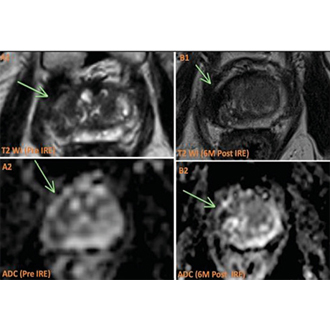

Необоротна електропорація як альтернативний метод лікування в онкології: клінічне застосування, сучасні можливості методу...